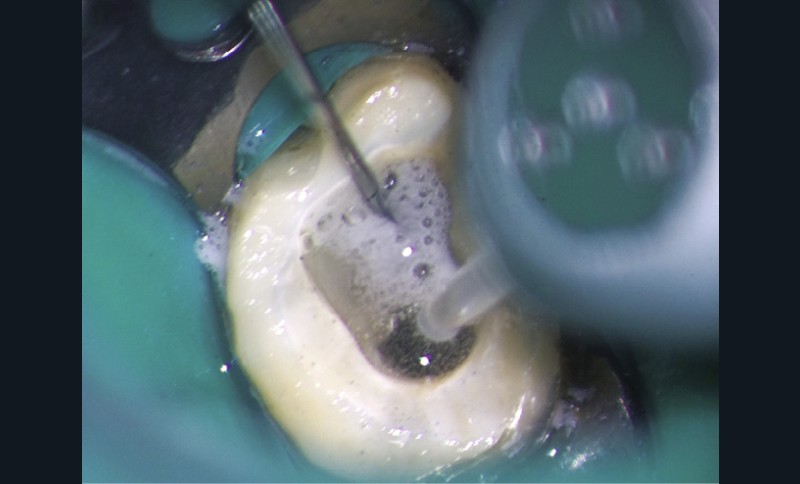

Endal, en 2011, montrait également, en utilisant le micro CT Scanner, l’insuffisance de nettoyage des isthmes inter-canalaires à nos techniques conventionnelles [19]. L’utilisation du laser Er:YAG devenait alors incontournable dans le nettoyage de ces isthmes et des zones non instrumentées (fig. 2 et 3).

Cette pénétration s’étend de la chambre pulpaire au réseau canalaire, isthmes, deltas apicaux et tubulis dentinaires. Il a été démontré que l’effet de cavitation pourrait permettre la destruction des bactéries à des profondeurs de 300 à 400 µm au sein des surfaces irradiées [20].

L’un des problèmes majeurs en endodontie reste les contraintes inhérentes à la dynamique des fluides, dans un espace canalaire confiné [27]. Ce phénomène physique empêche, en l’absence de turbulence, l’irrigant d’être véhiculé dans la zone apicale [28] et dans les zones non instrumentées et d’exercer son action solvante et antibactérienne.

Si l’étude de Peters [18] nous montre que l’instrumentation laisse 35 % du volume canalaire non instrumenté, Ricucci et Siqueira montrent que la préparation physico-chimique n’élimine que partiellement les tissus nécrotiques à l’entrée des canaux latéraux, des isthmes et des ramifications apicales, en laissant des tissus enflammés et infectés, en association avec des lésions apicales [29] (fig. 4 et 5).

L’hypochlorite de sodium, communément utilisé comme irrigant pour ses propriétés antibactériennes et solvantes, se doit d’être véhiculé pour atteindre ces zones retranchées [30]. Le laser Erbium permettra d’activer localement cette solution, augmentant la densité énergétique au sein de la zone ciblée, et donc de la véhiculer. Cette solution activée par le laser se fera à un faible niveau d’énergie avec des pulses courts, afin de rester dans un mode subablatif, et de permettre la formation d’une onde de choc initiatrice d’un phénomène photo-acoustique. Ceci tout en évitant tout risque de dégradation des parois dentinaires, d’échauffement, et de dommages thermiques [31].

Le tip du laser reste dans la cavité d’accès, remplie d’hypochlorite de sodium, renouvelée en continu, le spray de pulvérisation de la pièce à main fermé (le principe, relativement complexe, peut être simplifié).

Le passage du laser est répété plusieurs fois, en début, au milieu et en fin de préparation. Un protocole peut alors être proposé : 40 mJ ; 20 Hz (fig. 7). L’utilisation de biocéramiques Bioroot (Septodont) ou Total Fill R (FKG) permet de sceller le système ainsi nettoyé, en assurant une action biologique de longue durée [46] (fig. 8a à c).